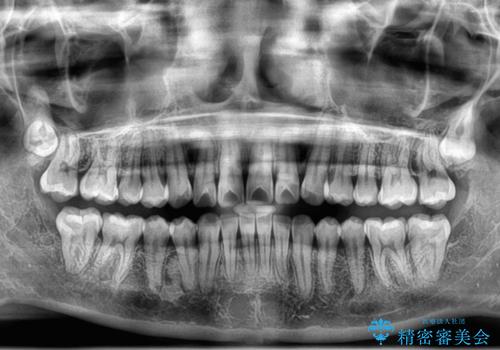

- 上下前歯のデコボコとディープバイトを気にして来院された患者様です。

歯列全体に叢生があり、舌の突出癖が認められたため、突出癖が改善されない場合には口元が突出するリスクが考えられました。

マウスピースでもワイヤーでも対応可能でしたが、煩わしいことは避けたいとのことで、舌のトレーニングをしっかりと行っていただきながら、ワイヤー装置にて矯正治療を行うこととしました。

なかなか舌の突出癖が改善できず、上下前歯が非接触となる期間が長く続きました。

アンカースクリューの活用と、舌のトレーニングを何度も指導し、出っ歯になることなく無事に治療を終えることができました。